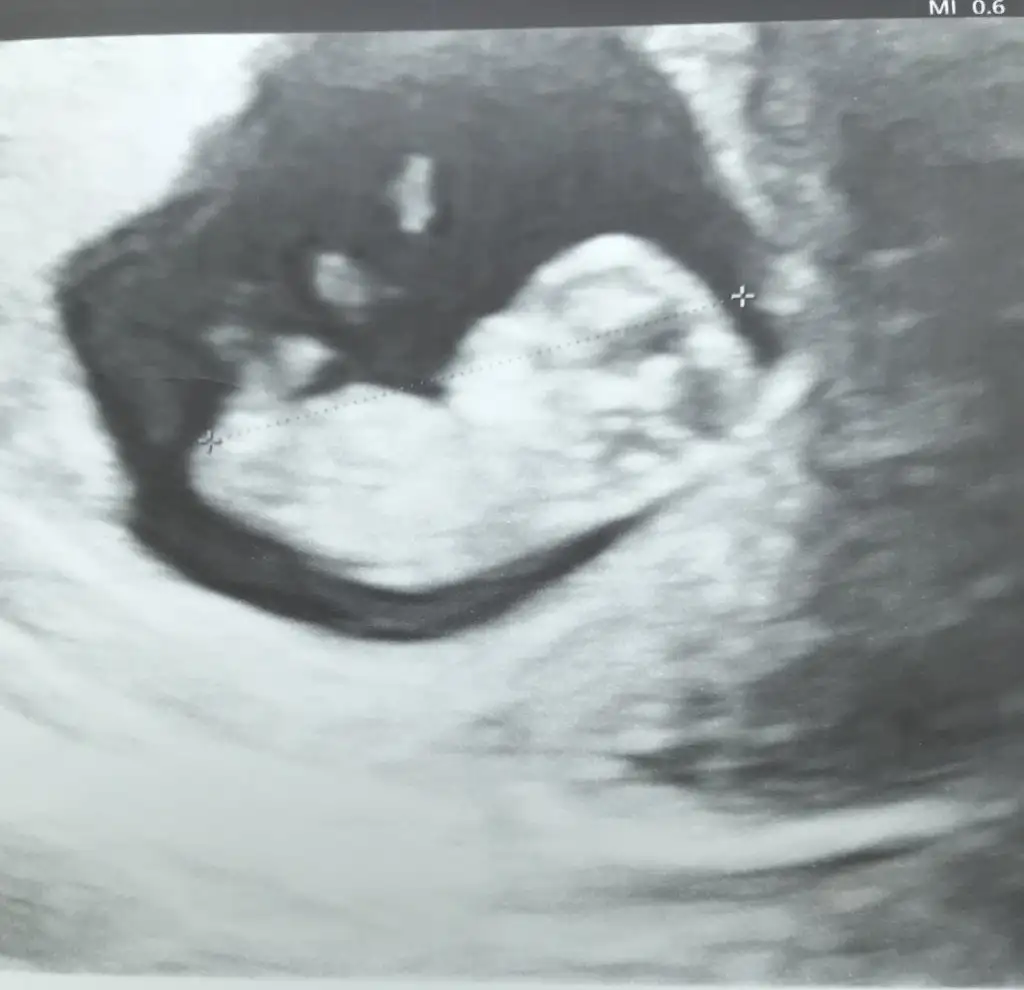

Ikra meyra Ikra meyra merhaba banada tahminde bulunur musunuz?🥰 ve anlayan diğer arkadaslarda tahminde bulunursa cok sevinirim😍